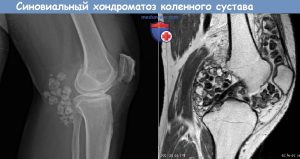

Диагностика заболевания включает в себя осмотр, сбор анамнеза, рентгенографию сустава (плотные хондромные тела явно видны), МРТ исследование, которое дает информацию об изменениях в хряще и в синовиальной оболочке сустава.